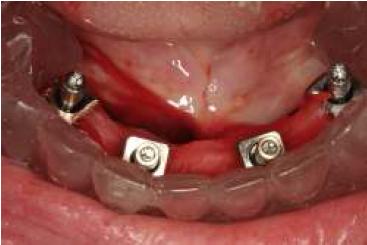

La planificación se realizó por medio de una ortopantomografía (fig. 5), evitando la utilización de cone-beam, siguiendo nuestro objetivo de realizar un tratamiento con un bajo costo. Al momento de la cirugía la paciente se encontraba premedicada con amoxicilina de 500 mg cada 8 h desde el día anterior15,16, ibuprofeno 400 mg cada 8 h10, comenzando 1 h antes de la cirugía17 y colutorios de clorhexidina al 0,12%, habiendo iniciado el tratamiento 48 h antes del procedimiento quirúrgico4. En el pabellón se probó nuevamente la guía multifuncional en boca (fig. 6), se anestesió a la paciente para luego realizar una incisión crestal desde la zona del primer molar derecho a la zona del primer molar izquierdo10,15,18, con incisiones liberadoras bilaterales, para luego realizar la disección subperióstica lingual y vestibular18. Con la plantilla radiográfica proporcionada por el fabricante se seleccionó sobre la radiografía panorámica el largo de los implantes a colocar. La cantidad de tejido óseo en sentido vestíbulo-lingual observada durante la cirugía fue de 5-6 mm, por lo que los implantes utilizados fueron implantes cónicos Strong SW de hexágono interno (SIN®, Sao Paulo, Brasil) de 3,8 mm de diámetro. Con la ayuda de la guía como referencia, se colocó 2 implantes distales, uno en cada lado, en la zona de los primeros premolares, inclinados a distal5, teniendo una longitud de 13 mm. Otros 2 implantes se colocaron a cada lado de la línea media mandibular, con una longitud de 15 mm. Se comprobó que los 4 implantes tuviesen una estabilidad primaria superior a los 30 N/cm (fig. 7). Se instalaron pilares Mini-Abutment y cilindros de protección de pilar, también teniendo como referencia la guía multifuncional. Se eligió suturar los tejidos con sutura no reabsorbible 4-018,19 (Seda, Ethicon, Johnson & Johnson, Brasil), siguiendo nuestro objetivo de disminuir los costos del procedimiento, y se envió a la paciente a la sala de recuperación (fig. 8).

Luego de un tiempo de recuperación para la paciente (30 min aproximadamente) se retiraron los cilindros de protección y se instalaron los transfer (fig. 9), se realizó entramado con seda dental entre ellos y se ferulizaron con acrílico en estado arenoso con método de goteo (Duralay®, Reliance Dental Mfg. Co., Worth, IL, EE. UU.) (fig. 10). Nuevamente se probó la inserción y posicionamiento de la guía en boca, para que esta no interfiriese con los transfer o el acrílico. Se comprobó la correcta oclusión con la arcada antagonista.